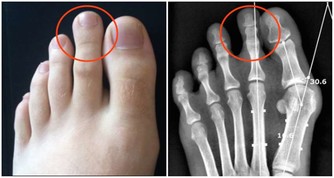

3.晚餐偏葷,血壓上升

晚餐內容若偏葷食,加上睡眠時的血流速度減緩,大量血脂就會沉積在血管壁上,進而引起小動脈和微小動脈的收縮,使外周血管阻力增高,易使血壓突然上升,也加速了全身小動脈的硬化過程。

5.血脂升高,加速動脈硬化

晚餐吃的太晚還會造成高血脂,加之人入睡後血流速度又明顯降低,從而導致血脂在血管壁上不斷沉積,長此以往,形成動脈粥樣硬化的危險係數自然就增大了。